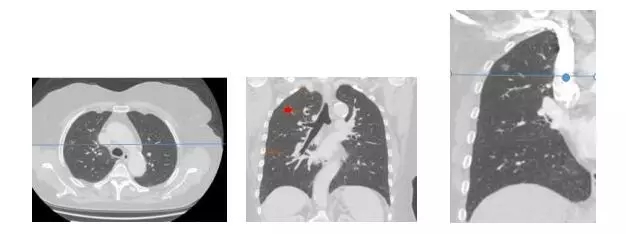

病例1:女,65岁,体检发现右肺上叶结节4个月,父亲患肺癌过世。CT:右肺上叶前段见类圆形磨玻璃影,长径约为0.8cm。术中快速病理:(右肺上叶肿物)贴壁状为主型腺癌,未见明确浸润证据术后病理:贴壁状原位腺癌,直径约0.6cm,未见明显浸润证据,切缘未见癌。